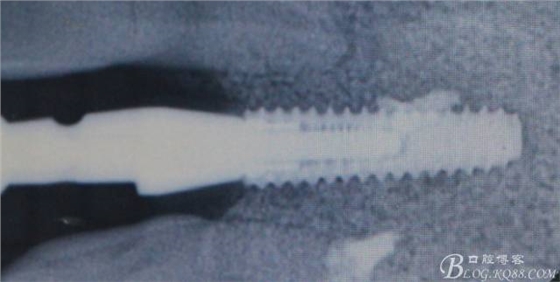

X光顯示沒有斷根

術(shù)后X光片。

骨高度穩(wěn)定。